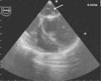

Perante o diagnóstico de endocardite mitroaórtica, iniciou tratamento antibiótico endovenoso empírico com vancomicina (30mg/kg/d) e gentamicina (5mg/kg/d). Iniciou também terapêutica anticongestiva oral com diuréticos (furosemida 1mg/kg/dose 12/12h e espironolactona 25mg 12/12h) e inibidores da enzima de conversão da angiotensina (captopril 1mg/kg/dose 8/8h). Posteriormente, isolou-se nas hemoculturas colhidas previamente ao início da antibioticoterapia, um Streptococcus mitis, sensível à antibioticoterapia previamente instituída. Teve uma evolução clínica inicial favorável com atingimento da apirexia no sexto dia de tratamento. Contudo, na segunda semana após a admissão hospitalar, houve reaparecimento da febre, associada a sinais e sintomas de ICC. Perante este agravamento clínico, a antibioticoterapia foi substituída por ceftriaxone (60mg/kg/d) e teicoplanina (10mg/kg/d), em associação à intensificação da terapêutica diurética, com aumento da dose de furosemida para 1mg/kg/dose 6/6h e administrada de forma endovenosa, mantendo a restante terapêutica nas doses e forma de administração previamente instituídas. As hemoculturas colhidas antes da substituição da antibioticoterapia vieram a revelar-se negativas. Nesta fase, realizou também um ecocardiograma transesofágico, que revelou vegetações em ambas as válvulas mitral e aórtica (Figuras 1 e 2), assim como um abcesso paravalvular miroaórtico. A função ventricular esquerda, nesta altura, apresentava-se ligeiramente comprometida.